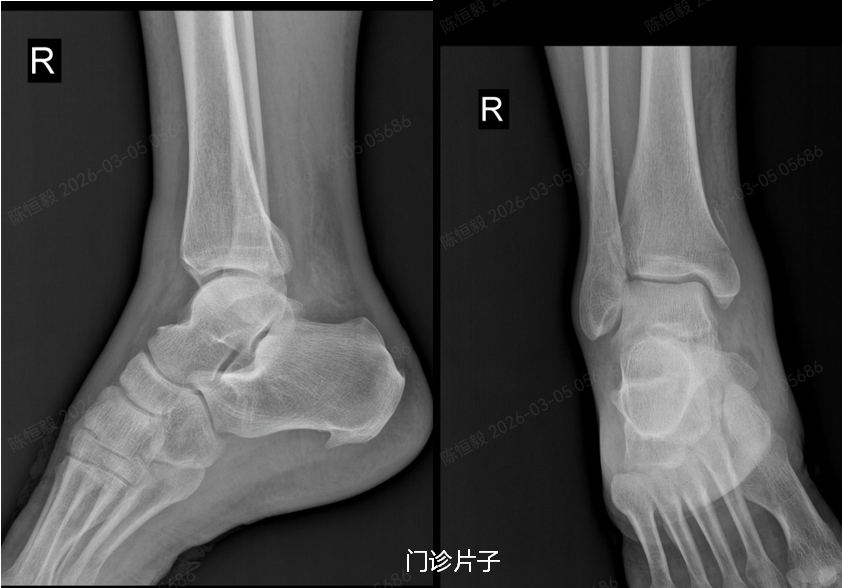

在北京积水潭医院郑州医院拍 X 光片后未见明显骨裂,王大爷更是觉得无需治疗,准备回家自行休养。

但接诊的足踝外科主任杨建义查看片子并仔细为其体格检查后,发现了异常,当即告知王大爷,其下胫腓部位大概率存在损伤,建议住院做进一步详细检查,排除隐匿性问题。

王大爷听从建议住院后,经完善体格检查及 CT 检查,最终确诊为复杂的 Maisonneuve 骨折:不仅存在下胫腓分离,还合并前踝 Chapute 结节撕脱骨折、后踝骨折、内踝骨折,同时伴有腓骨高位骨折。